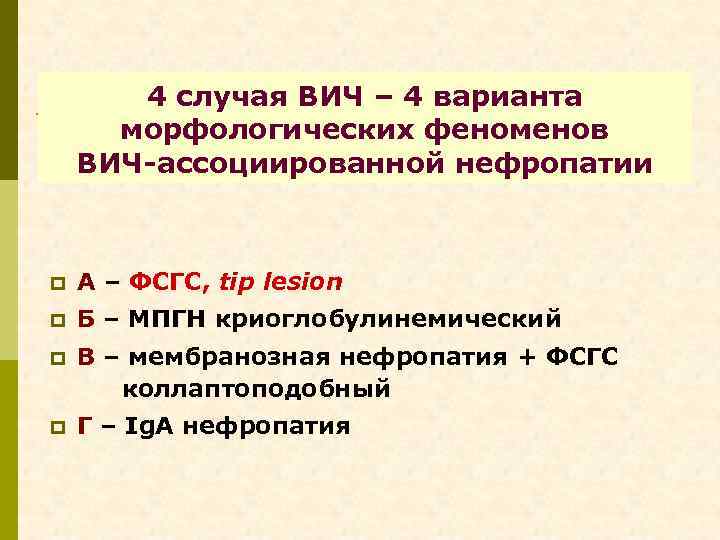

4 случая ВИЧ – 4 варианта морфологических феноменов ВИЧ-ассоциированной нефропатии p А – ФСГС, tip lesion p Б – МПГН криоглобулинемический p В – мембранозная нефропатия + ФСГС коллаптоподобный p Г – Ig. A нефропатия